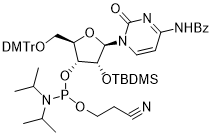

馬鞍山致研生物醫(yī)藥科技有限公司成立于馬鞍山市鄭浦港新區(qū)現(xiàn)代產(chǎn)業(yè)園。公司專(zhuān)注于生物小分子、醫(yī)藥中間體相關(guān)產(chǎn)品的研發(fā)和生產(chǎn),產(chǎn)品主要包括DNA亞磷酰胺單體、RNA亞磷酰胺單體、特殊單體以及按照客戶(hù)要求定制的RNA和DNA,并且公司提供定制合成等方面的研究服...

馬鞍山致研生物醫(yī)藥科技有限公司成立于馬鞍山市鄭浦港新區(qū)現(xiàn)代產(chǎn)業(yè)園。公司專(zhuān)注于生物小分子、醫(yī)藥中間體相關(guān)產(chǎn)品的研發(fā)和生產(chǎn),產(chǎn)品主要包括DNA亞磷酰胺單體、RNA亞磷酰胺單體、特殊單體以及按照客戶(hù)要求定制的RNA和DNA,并且公司提供定制合成等方面的研究服...